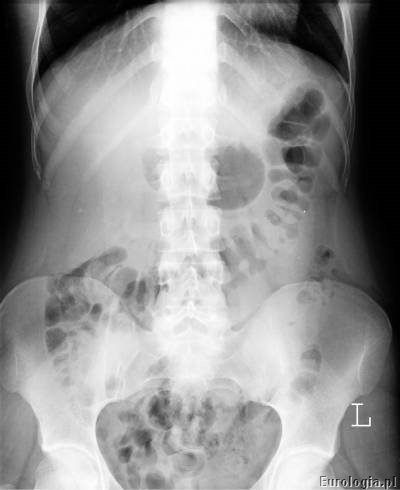

Pierwsze zdjęcie rentgenowskie po podaniu kontrastu w czasie urografii pokazuje tak zwaną fazę nefrograficzną – uwidacznia się warstwa miąższowa nerek. Już pierwsze zdjęcie wykonane podczas urografii w większości przypadków pozwala ocenić ilość nerek i ich położenie.

Urografia wykonywana jest w pracowni rentgenowskiej i trwa około 30 minut. W czasie badania pacjent układany jest w pozycji leżącej na plecach na stole rentgenowskim. Pierwsze zdjęcie wykonane przed podaniem kontrastu nazywane jest zdjęciem przeglądowym nerek i pęcherza, na którym możliwe jest uwidocznienie cieni mogących być uwapnionymi złogami w układzie moczowym. Kolejnym etapem badania jest dożylne podanie kontrastu przez wenflon wkłuty na przedramieniu pacjenta. Po podaniu kontrastu wykonywana jest seria zdjęć rentgenowskich w odpowiednich odstępach czasu. Czasami konieczne jest wykonanie tak zwanych późnych zdjęć urograficznych w sytuacji gdy w standardowym czasie nie uzyskano zakontrastowania układu kielichowo – miedniczkowego lub moczowodu.

Przykładowe badanie urograficzne :